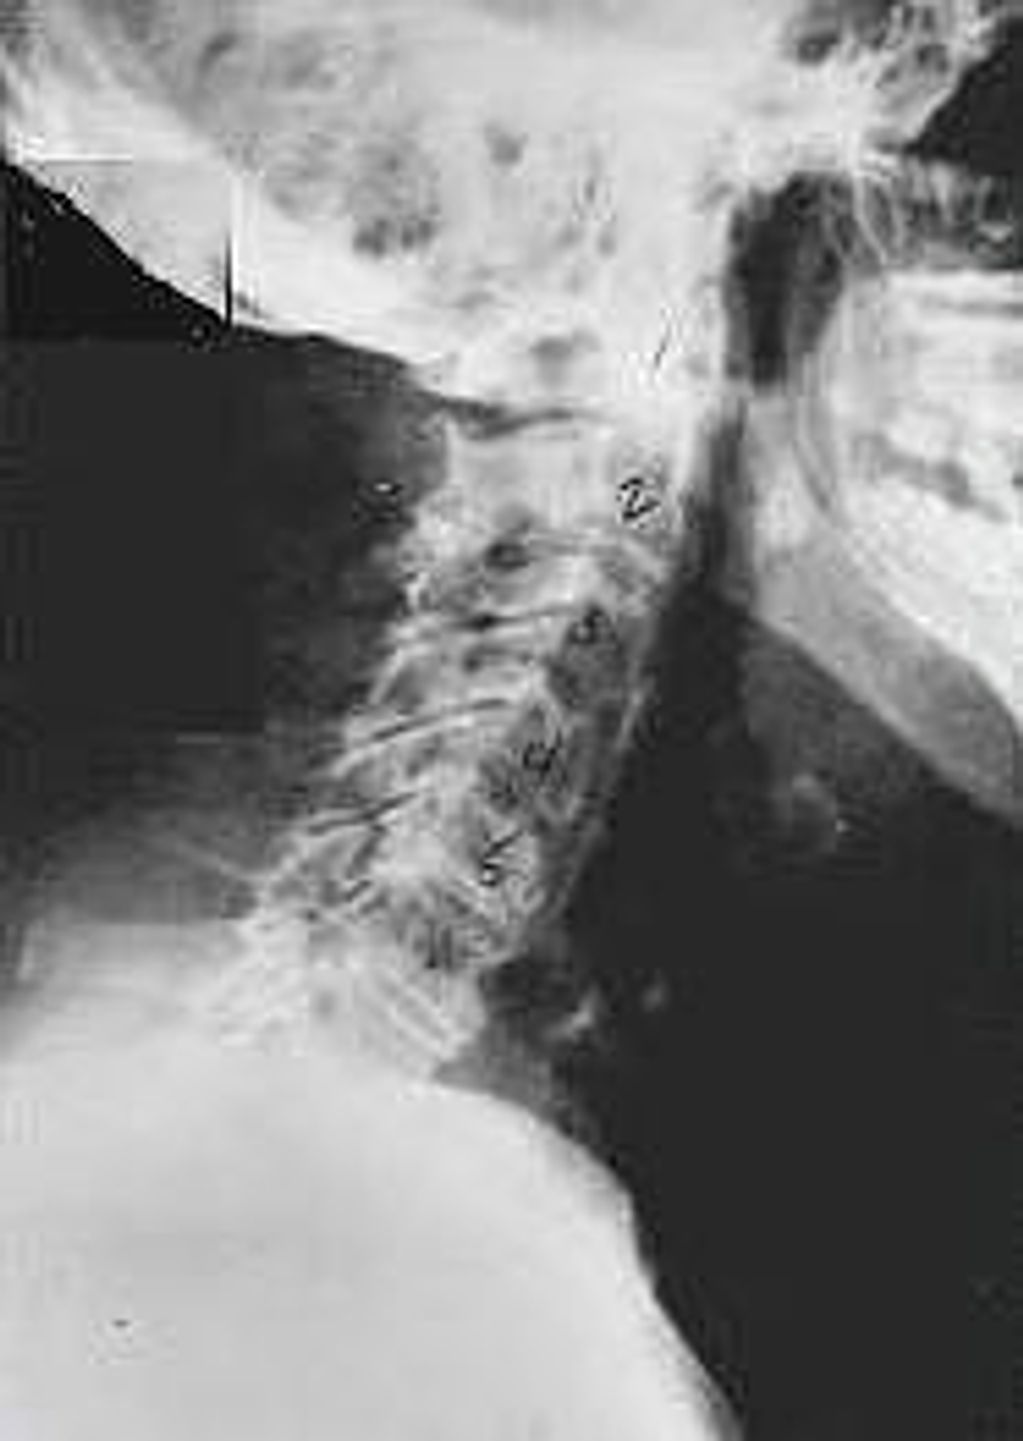

Phase One Subluxation Degeneration

Phase One Subluxation Degeneration is seen in subluxations that have been present for up to twenty years. This phase is characterized with a loss or change in the normal curve in the spine. On this example you can see that the normal forward (lordotic) curve is lost. This spine even has developed a reverse curve in the neck. The disc spaces have